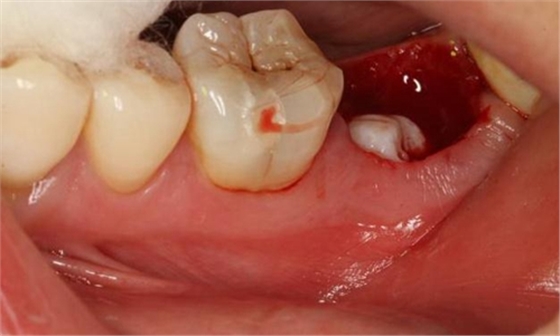

圖3.拔除47后的牙槽窩影像:

圖4.術(shù)后拔除的牙根: